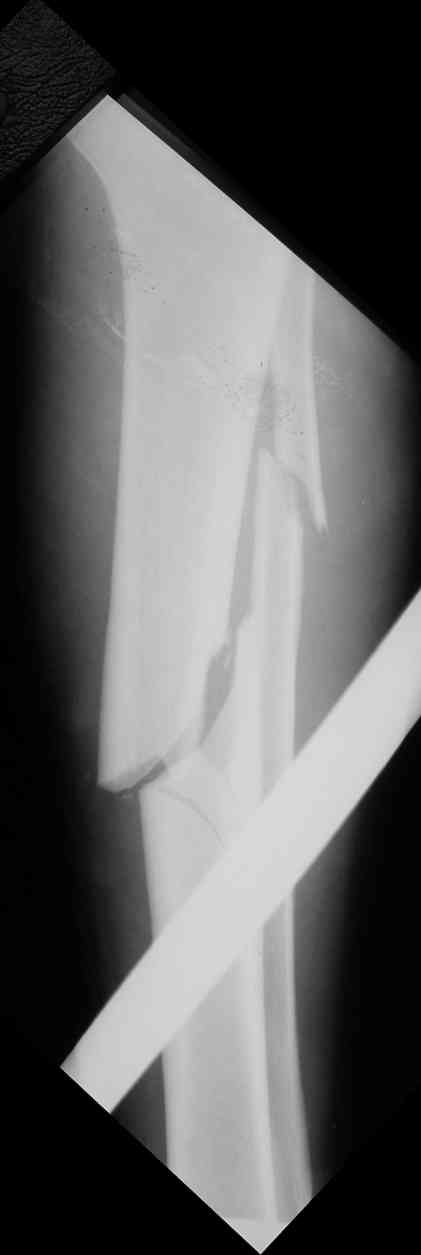

В отношении ранней нагрузки при спиральных переломах лучше не торопиться. По данному случаю необходимо достигнуть исчезновения щели между штифтом и внутреним кортексом по Rg. А так картинка прекрасная - и длина сегмента и репозиция. Можно поздравить, коллега!

Да, спасибо за интересные иллюстрации. Получилось очень симпатично. На большеберцовой кости непременно надо было винты? Там же был торцовый упор, перелом в средней трети?

Это при раздувании гвоздя, или сейчас? Если второе, то я не понял. А так - давление повышали до 80 ата, перестали нагнетать, когда перестало снижаться меньше 70.